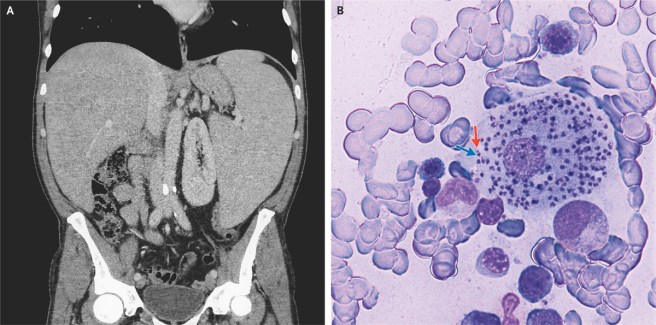

Visceral Leishmaniasis | NEJM 5 de fevereiro de 2019 ~ infectologia em geral Images in Clinical Medicine from The New England Journal of Medicine — Visceral Leishmaniasis Fonte: Visceral Leishmaniasis | NEJM Compartilhe isso: Compartilhar no X(abre em nova janela) 18+ Compartilhar no Facebook(abre em nova janela) Facebook Envie um link por e-mail para um amigo(abre em nova janela) E-mail Imprimir(abre em nova janela) Imprimir Curtir Carregando... Relacionado